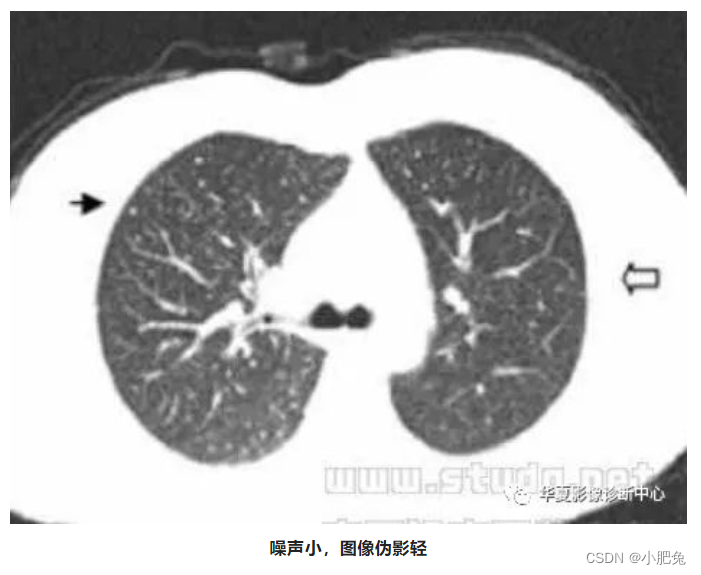

八、噪声引起的伪影

噪声的主要原因是入射射线光子数量不足。 如果扫描参数选择不当,或患者在扫描架内的位置偏移(偏离扫描野中心),可使入射射线光子数量不足,进而产生图像伪影(图像模糊)。

处理方法

正常情况下, 光子数越多信号越强、噪声越小, 反之则信号越弱、噪声越大。噪声所引起的伪影, 通常只要增加扫描条件即可避免。其他也可采用专用滤过算法, 也可使噪户伪影减弱。